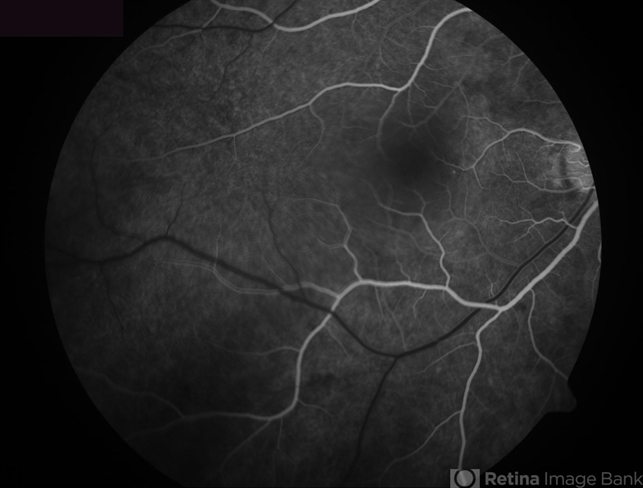

- Central Serous Chorioretinopathy

- central serous chorioretinopathy (CSCR)

- Fluorescein angiogram, early phase, showing a very small hyperfluorescent spot nasal to the fovea.